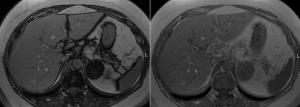

A 63-year-old man with NET metastatic to the liver undergoes MRI for evaluation of response to therapy. Based on the imaging, what is your diagnosis?